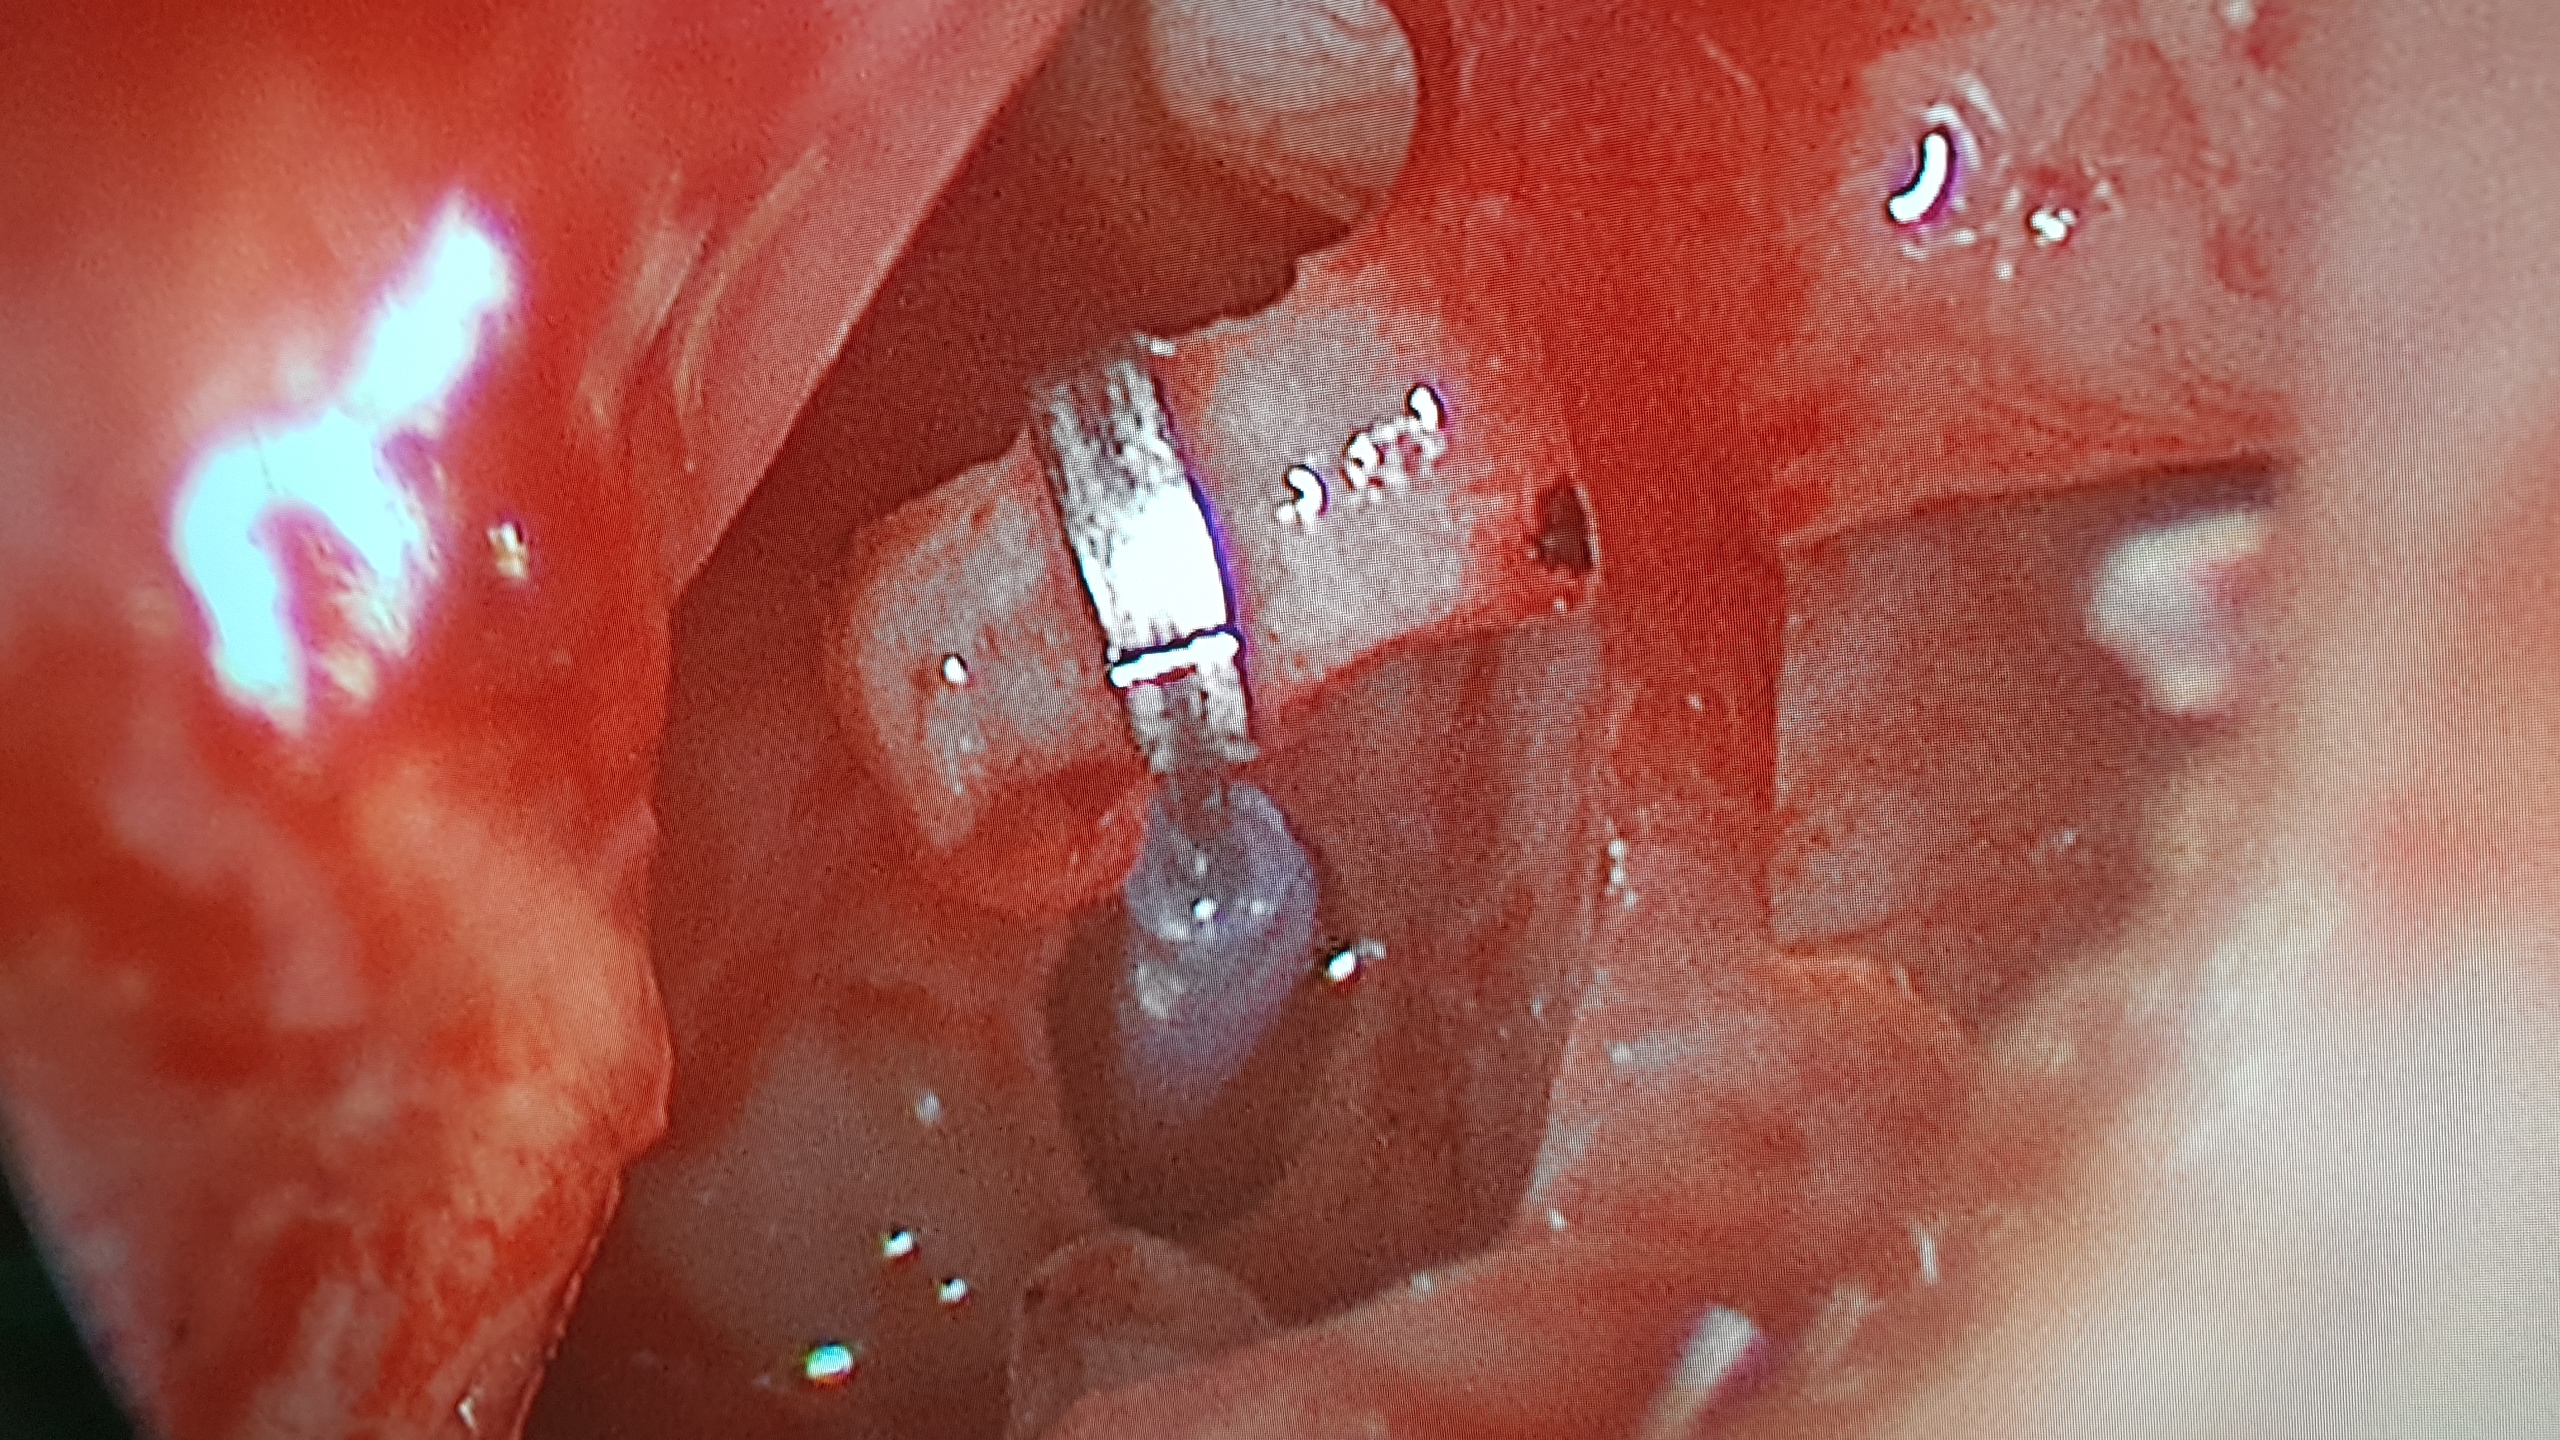

University of the Witwatersrand, , Department of Otorhinolaryngology, 3D Temporal Bone Workshop, Baragwanath Hospital, Soweto January 19, 2025 Read more

University of the Witwatersrand, , Department of Otorhinolaryngology, 3D Temporal Bone Workshop, Charlotte Maxeke Johannesburg Academic Hospital, JHB January 19, 2025 Read more

University of FS, Department of Otorhinolaryngology3D Temporal Bone Workshop, Bloemfontein January 19, 2025 Read more

University Of KZN, Discipline of Otorhinolaryngology, 3D Temporal Bone Workshop, Durban January 19, 2025 Read more

University Of Stellenbosch, Division Of Otorhinolaryngology, Scull Base Surgery Course January 19, 2025 Read more